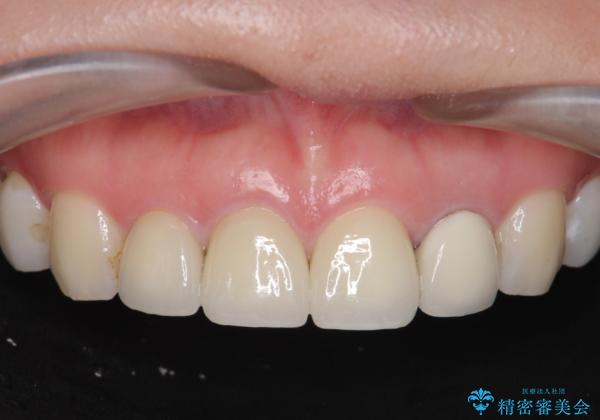

[根管治療・セラミッククラウン] 前歯の痛み・見た目を改善したい

- 前歯の痛み、不自然さを解消したいと来院されました。

X線写真検査より感染根管による根尖性歯周炎、レジン前装冠の欠け、コンポジットレジン充填によるツギハギになってしまった歯が認められました。

それぞれの問題点に対し、感染根管治療・ジルコニアクラウンの製作を行い感染の除去・審美性の回復を計画します。

感染根管治療を行ったことで痛みはなくなり、ジルコニアクラウンによる再補綴を行ったことで自然な透明感を再現した歯になり審美性を回復することができました。